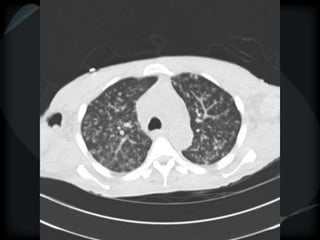

miliary

random